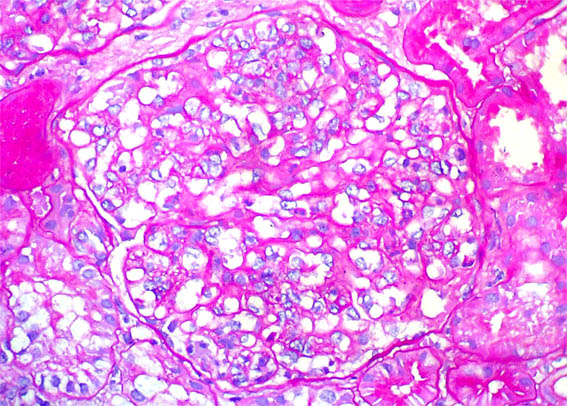

Figura 4.

PAS, X400.